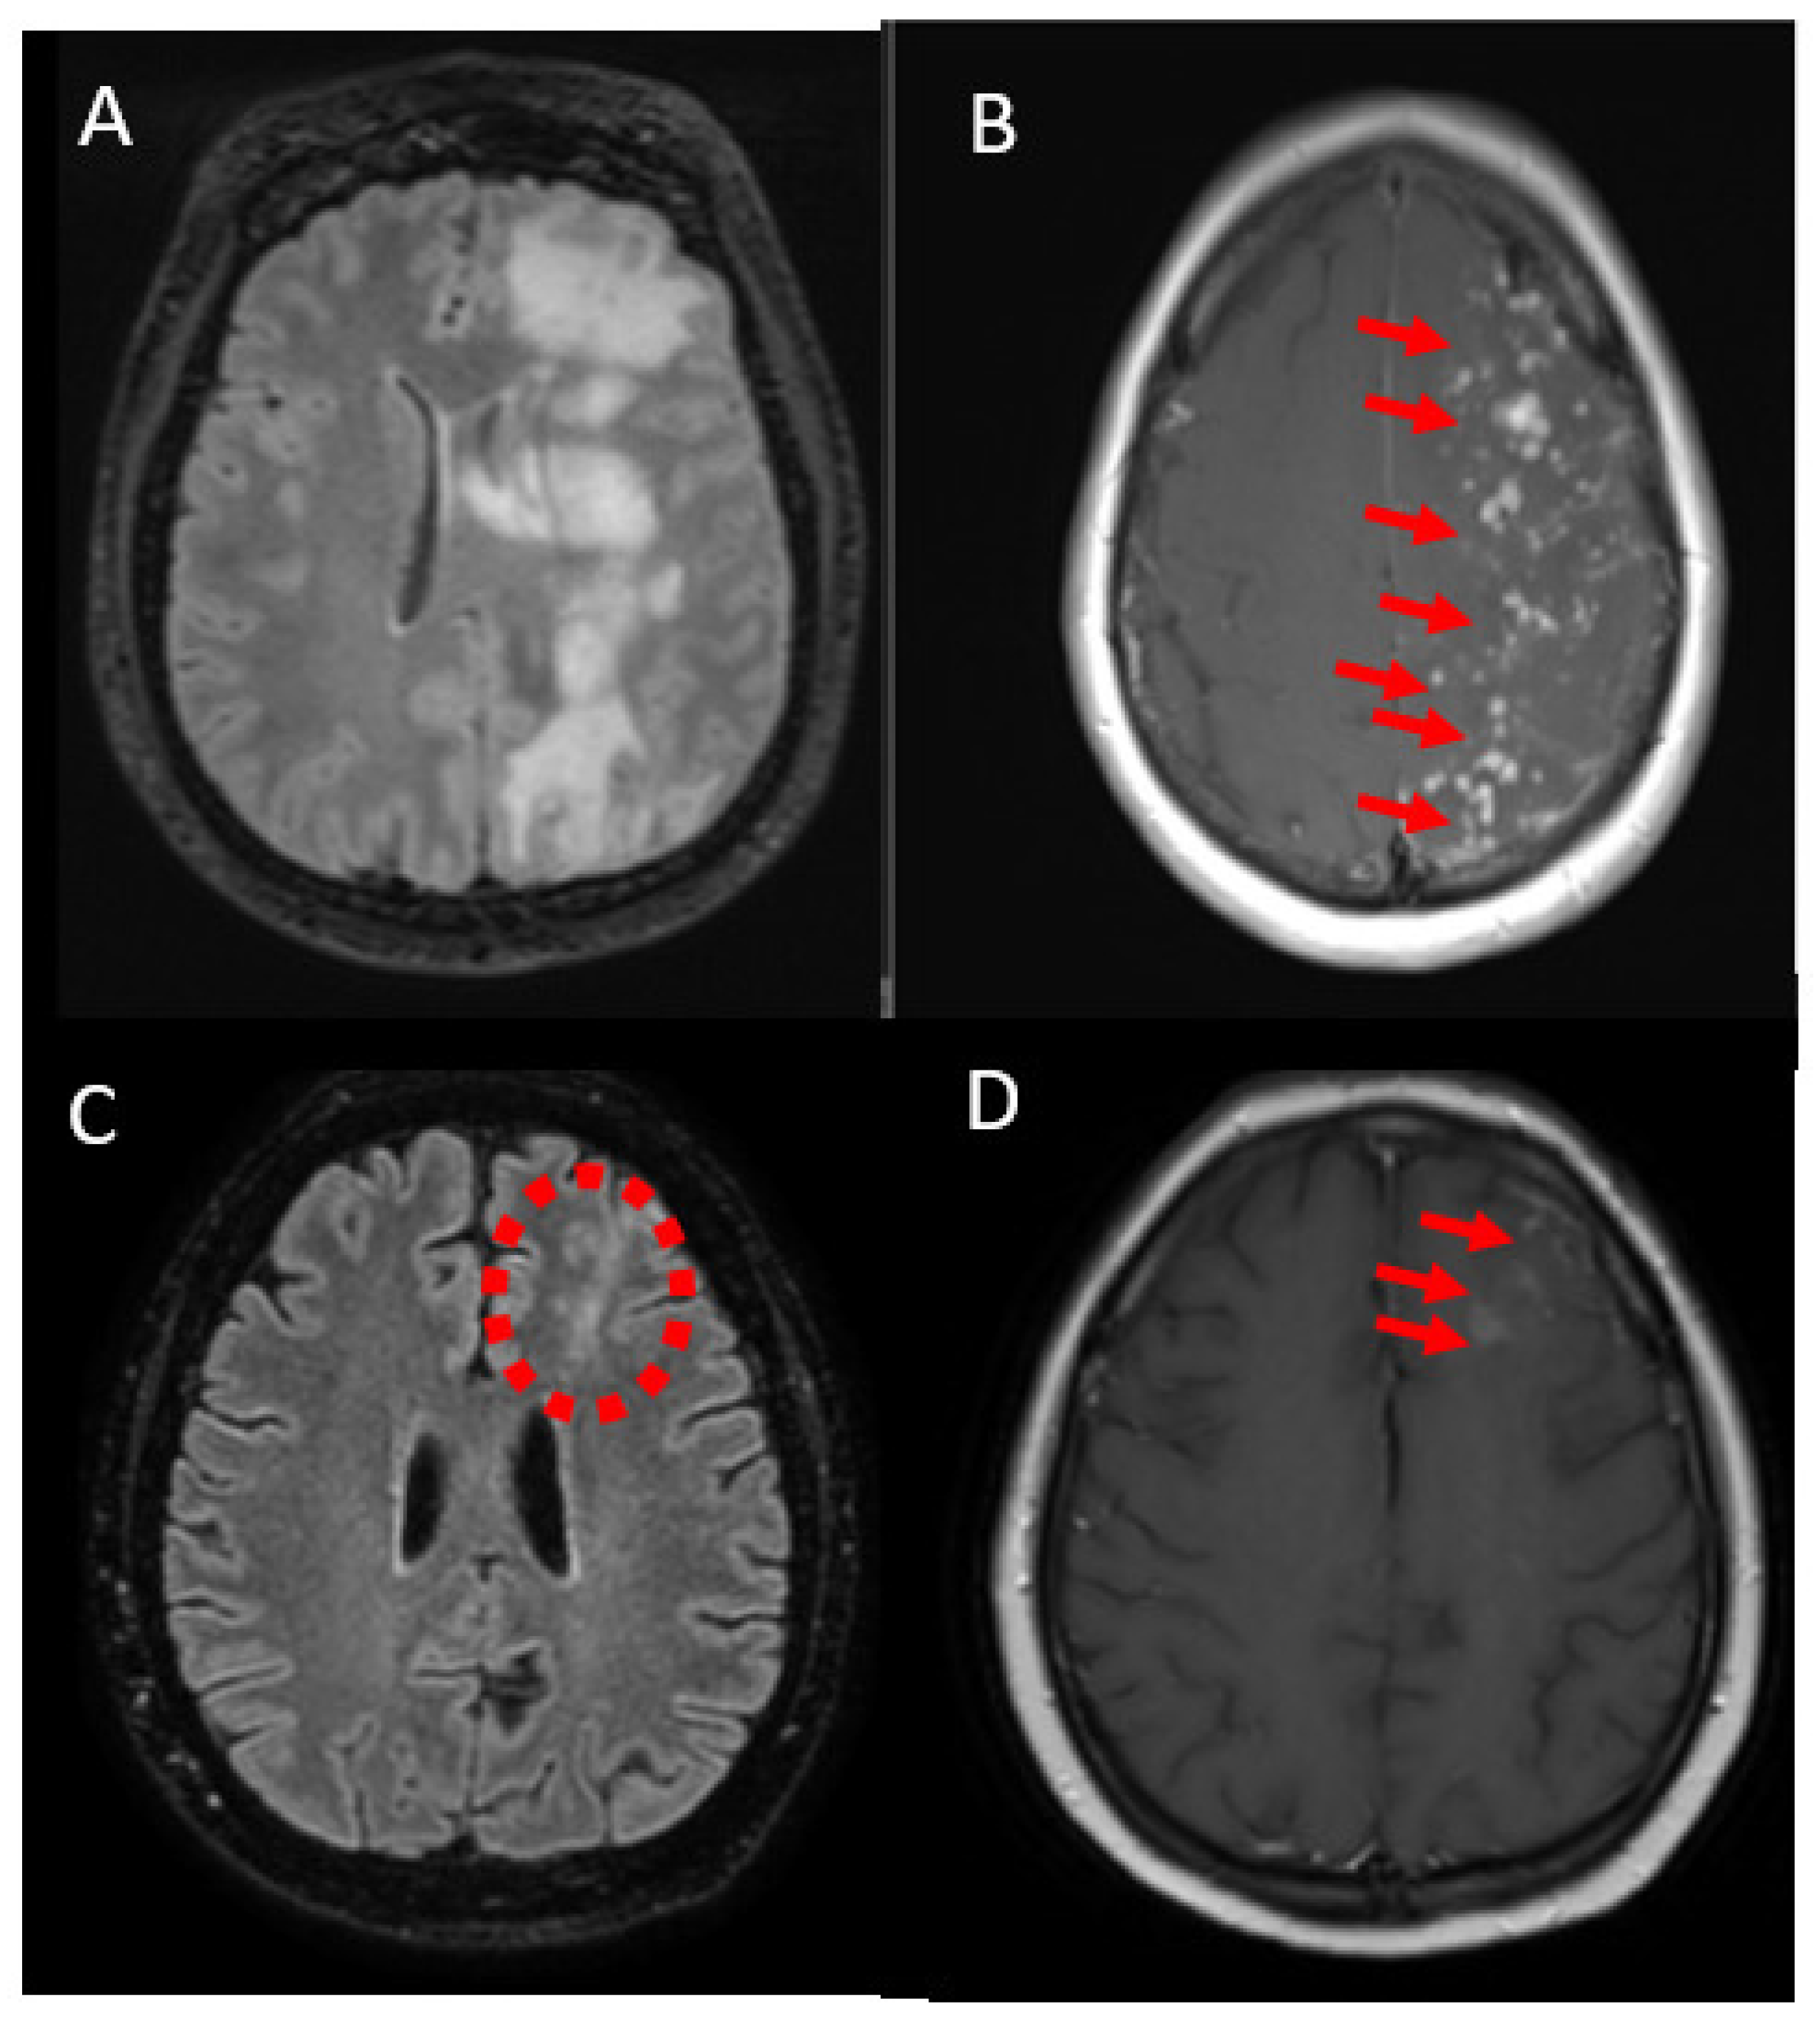

| Case 3 F/49 | Flow diverter stent/ supraclinoid segment of left ICA | 6 months | gait disorders, right-sided hemiparesis, partial seizures of the right upper limb, mild cognitive impairment | Enhancing lesions, vasogenic edema, low SWI signals | Yes-chronic necrotizing granulomatous inflammation | Steroids **/improvement, recurrence after tapering | 1 year |